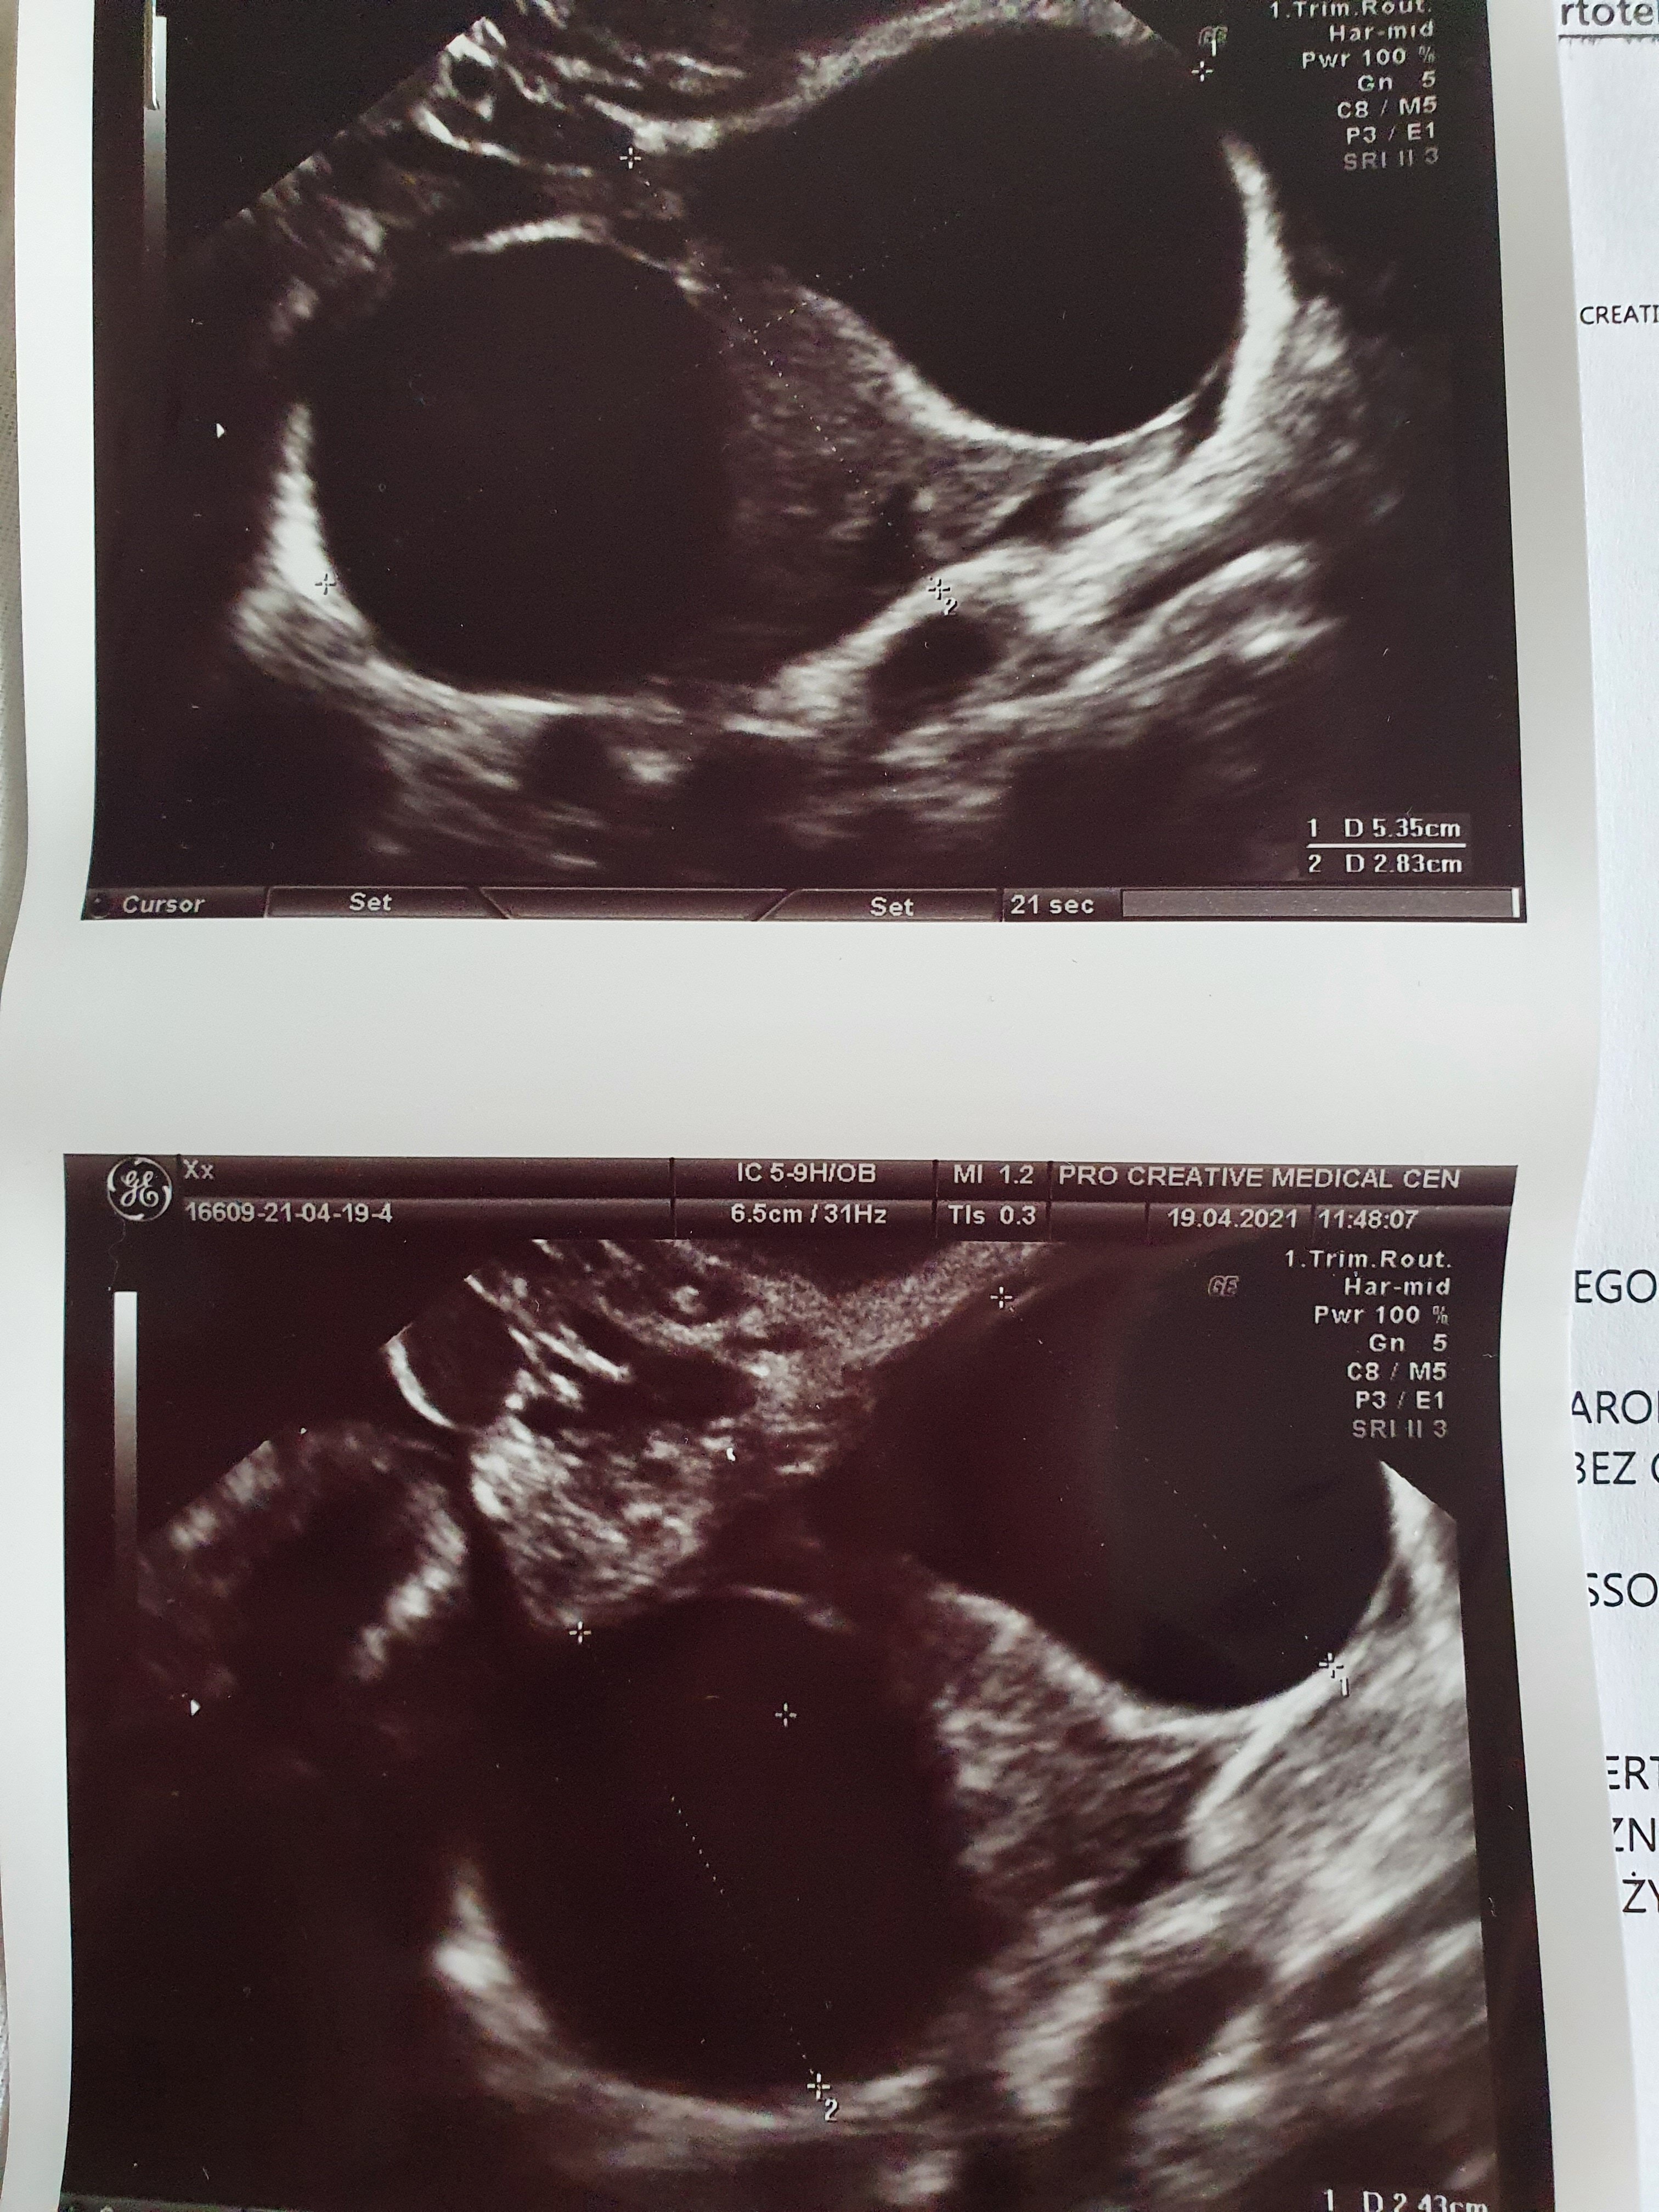

Cześć! Byłam u lekarza, pęcherzyk mam w macicy wg pomiarów 4tc i 6dni, na razie bez zarodka i ciałka żółtego. Już wiem co mam w tym lewym bolącym jajniku - dwie cysty, jedna ma wyrzuty krwi, druga jest jakaś dziwna do obserwacji czy nie jest pozamaciczną. Dzisiaj zrobiłam kolejna betę, za trzy dni mam skontrolować przyrost

Za tydzień kolejne usg, żeby kontrolować czy się zarodek w jajniku nie pojawi i czy cysty się nie powiększają jeśli tak to szpital. Jeśli przez ten tydzień zacznę plamic mam od razu jechać do szpitala. Przepisał mi duphaston. Ta ciążą też nie jest do końca normalna, ale mam nadzieję, że się wszystko ułoży